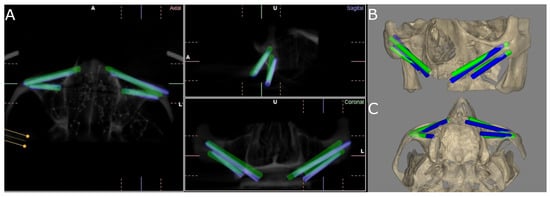

2.3. Measurement Procedure